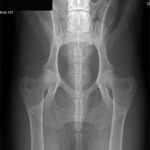

Giant Schnauzer Population Analysis “To safeguard and manage genetic diversity of each breed, breeders need to make informed decisions based on the specific characteristics of their breed. Since the previous population analysis in 2015, we have expanded our understanding of … Continue reading →